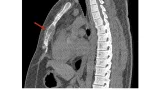

外来に戻り説明を終えた後, 昨日依頼のあった大腿骨転子部骨折の超高齢者が来院.

車イス上で痛みの訴えは少ないものの, X線では明らかな転位あり.

手術前提で検査をオーダしました.

17時前に外来にもどって, 検査の結果を確認したところ, 貧血, 慢性腎臓病, 尿路感染があり.

輸血, 輸液, 抗菌薬投与を行って治療して, 状態が改善したら手術を行うことをご家族に説明し, 入院していただくことになりました.